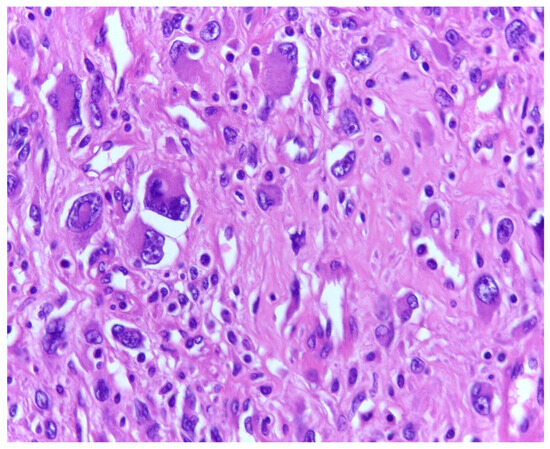

3.1. Tumor Grade